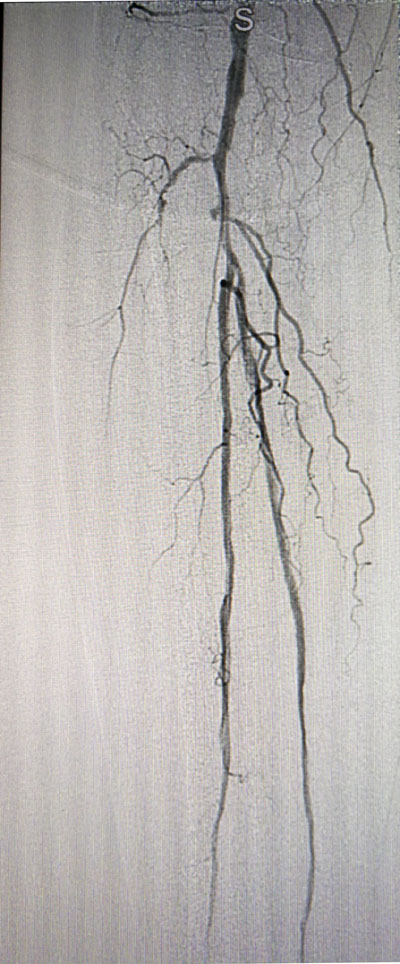

放射科導(dǎo)管室內(nèi)做好了術(shù)前準(zhǔn)備,患者由無創(chuàng)呼吸機(jī)及各種循環(huán)支持下開始介入手術(shù),術(shù)中重癥監(jiān)護(hù)科嚴(yán)密觀察患者的生命體征,內(nèi)分泌科醫(yī)生負(fù)責(zé)手術(shù),患者下肢血流極差,膝下僅存一條多處嚴(yán)重狹窄的腓動脈供血,主要供血的脛前動脈及脛后動脈均長段閉塞,順行穿刺成功后導(dǎo)絲下行困難,故采用踝下脛后動脈逆穿對接技術(shù)成功通過病變。經(jīng)過近5個小時的奮斗,手術(shù)順利完成,患者腓動脈及脛后動脈血流通暢,血流直達(dá)足底動脈環(huán),患者感到足部逐漸溫暖,術(shù)后清創(chuàng)時患者創(chuàng)面血流豐富。

治療后